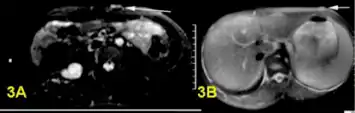

-

a,b)Bright plexiform neurofibroma -

Histopathology of neurofibroma: A spindle cell lesion composed of slender fibroblast-like cells with storiform pattern and very low amount of stroma.[16] -

Neurofibroma marked for biopsy, right upper back